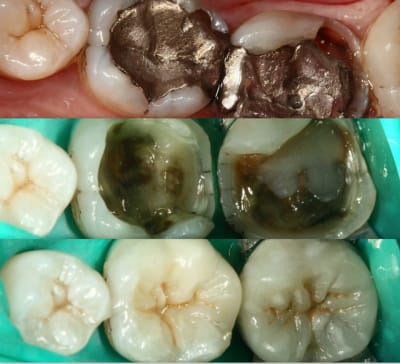

Onlay emax à 5 ans... contrôle la semaine dernière...

Dans cette situation, que donnerait un composite ?

mg 5091 rijxb8 - Eugenol

Img 7865 rjs3gn - Eugenol

tiens c'est bizarre , sur la dernière photo de cingulum (magnifique travail d'ailleurs) , la dent est toujours sur l'arcade alors que le joint semble être juxta voir sous gingival. Il m'a semblé avoir lu plus haut qu'un joint en compo ça se carie automatiquement au bout de cinq ans....

Allez cingulum , arrête de nous faire marcher, fais peter la radio avec la reprise de carie, l'endo, l'IC et la CCM!